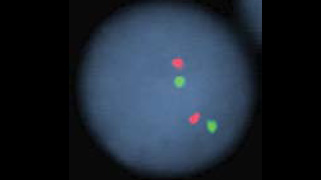

1313q14Vysis LSI 13 SpectrumGreen            2VIEW IMAGE

2121q22.13-q22.2Vysis LSI 21 SpectrumOrange Probe            1VIEW IMAGE